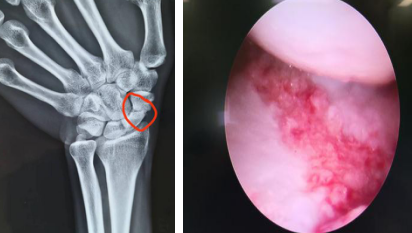

5月7日,齐主任手术团队为小刘进行了“机器人导航+关节镜辅助下左舟骨骨折复位取髂骨植骨内固定术”。术中关节镜探查见:左舟状骨骨折端部分骨质硬化,周围滑膜增生,髓腔内部分坏死。关节镜下用一次性磨钻,磨除骨折两端硬化骨质及坏死骨质至骨折端有新鲜血液渗出,关节镜下一次性刨削器刨除滑膜组织。再于右侧髂骨处开窗式取松质骨,将准备好的松质骨剪成小块儿通过关节镜套筒植入左舟骨骨折端缺损处。完成植骨后,机器人导航下予以精准3D定位,螺钉内固定。手术顺利,全程3个多小时。

术前(左图)关节镜下植骨(右图)